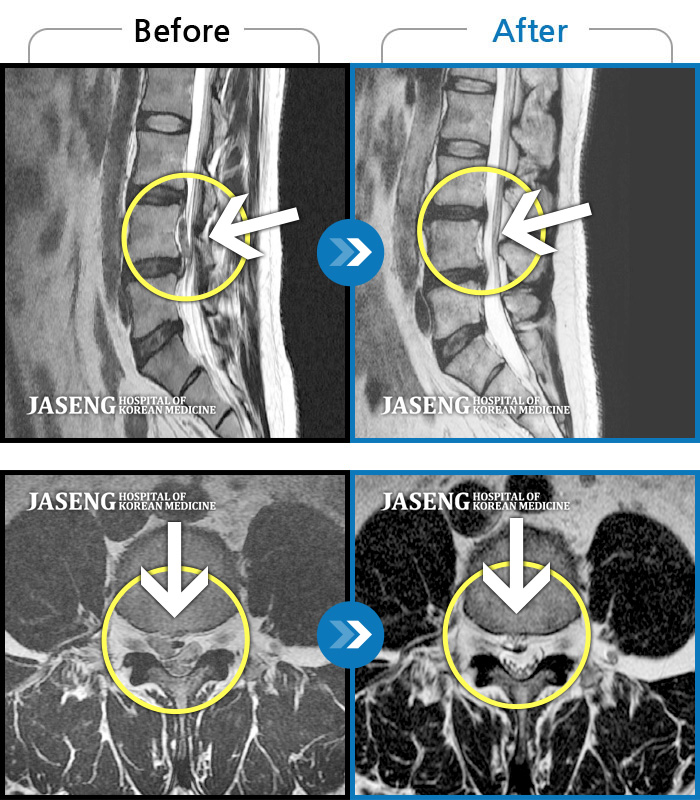

허리디스크

도움받은 사례

강남 · 강만호 원장

허리통증이 심해서 숙이기 어렵고 차에서 내리기 힘들었습니다.

촬영시기

2021.01.06 ~ 2025.03.10

2025.03.20

조회수 13,018